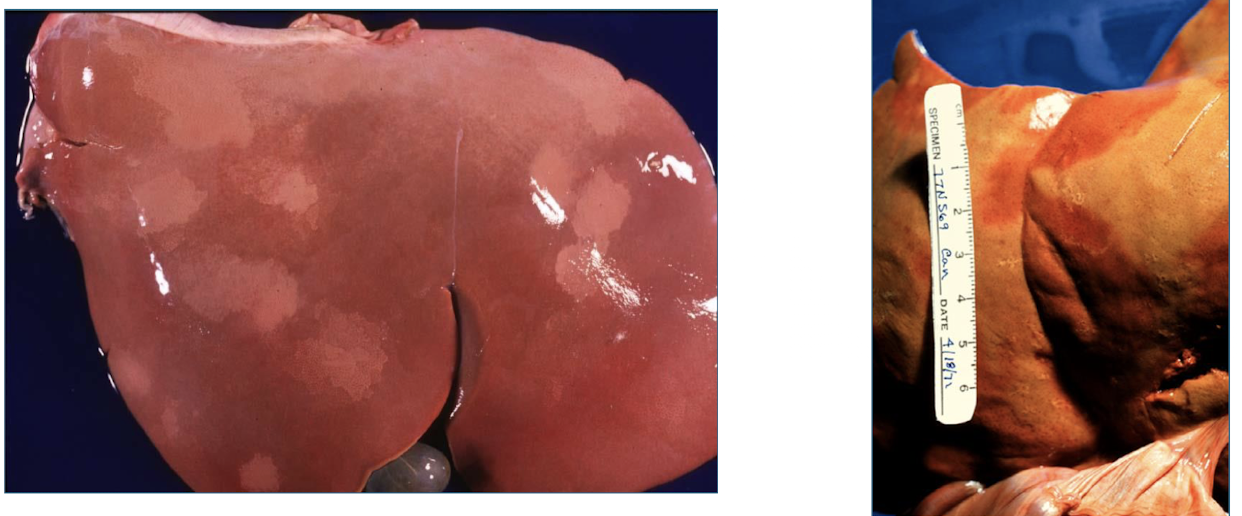

Why do you see pallor?

postmortem pressure on organs can force blood out of tissues → “pale imprints” (rib imprints)

T/F: Pallor can be caused by postemortem bacterial proliferation in the liver.

TRUE - must differentiate from antemortem necrosis

hemoglobin imbibition

reddish discoloration of tissue by hemoglobin from lysed erythrocytes

Where will you normally see hemoglobin imbibition?

bile imbibition

greenish discoloration from leakage of bile through wall of the gallbladder or bile ducts